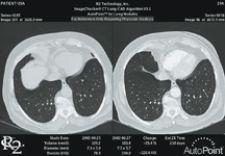

R2 Technology integrated its ImageChecker CAD CT Lung solution into Vital Image's Vitrea workstation to optimize workflow demands of lung examiniations

But a generic 3-D solution is not enough – the need for advanced visual applications goes beyond the radiology department, as oncologists, neurologists and cardiologists are also routinely consulting images produced from PET, SPECT, CT and MR. The good news is that PACS vendors are catching on and designing specialty applications for specific focuses, such as colon, cardiology, lung, breast and bone that incorporate 3-D and 4-D into clinical workflow – replacing generic 3-D applications.

Viewing high-volume 3-D and 4-D data sets is becoming prevalent across specialties, and specific applications for colon, cardiology, lung, breast and bone are now incorporating 3-D and 4-D into clinical workflow.